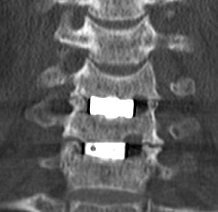

74歳 男性 腰椎圧迫骨折

1月に尻餅をつき、第2腰椎圧迫骨折があり、他院で保存的治療を受けられていました。

9月に腰痛が強くなって来院されました。新たに第3腰椎圧迫骨折がみられました。

第2腰椎骨折は数か月の間に進行して、ひしゃげていましたので、第3腰椎もそのようになる可能性がありましたので、

人工骨を注入する手術を局所麻酔で行いました。